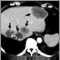

CT of the abdomenDefinition Return to top

An abdominal CT scan is an imaging method that uses x-rays to create cross-sectional pictures of the belly area. CT stands for computed tomography.